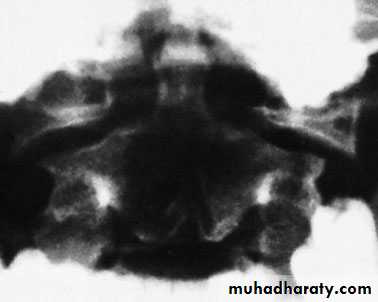

C1 ring fracture

Sudden severe load on the top of the head may cause

a ‘bursting’ force which fractures the ring of the atlas

(Jefferson’s fracture). There is no encroachment on

the neural canal and, usually, no neurological damage.

The fracture is seen on the open-mouth view (if the

lateral masses are spread away from the odontoid peg)

and the lateral view. A CT scan is particularly helpful

in defining the fracture.

Fracture of C1 ring Jefferson’s fracture – bursting

apart of the lateral masses of C1.Treatment